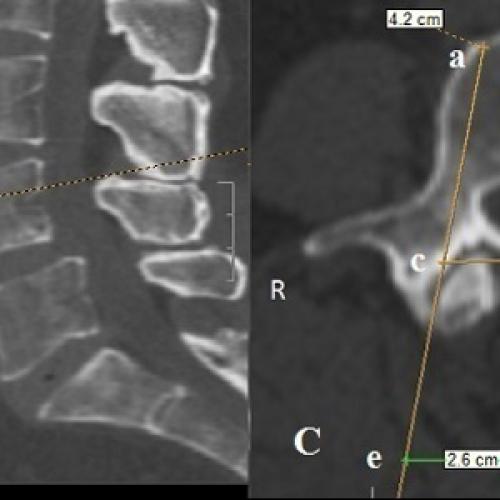

Асистолия может произойти рефлекторно (внезапно) при еще сохранившемся тонусе миокарда или постепенно (при сохранившемся тонусе миокарда или при его атонии). Остановка сердца чаще всего происходит в диастоле и значительно реже встречается в систоле. На рис. ниже на ЭКГ показан агональный ритм , переходящий в асистолию .

На рис. ниже приведена ЭКГ при крупноволновой и мелковолновой фибрилляции желудочков.